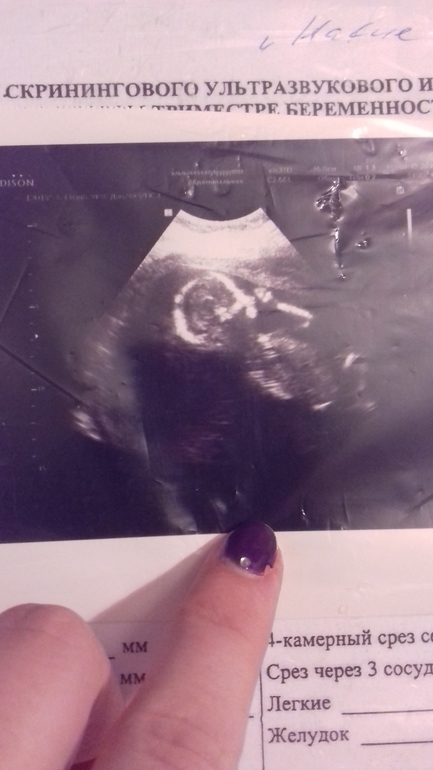

У нас будет мальчишка)))

Поздравляю вас! Здорово, когда мечты сбываются!)) У меня тоже 16 недель и 4 дня, но пол еще не знаем)) Ждем второй скрининг..

Спасибо))) Мы тоже ждали 2 скрининга))Но это было внеплановое узи)